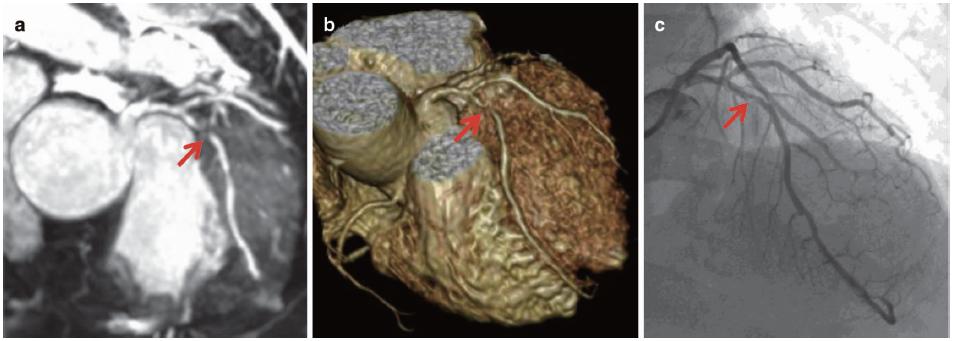

图7.4 患者男性,65岁,胸痛,LAD重度狭窄。采用1.5T MR获得非对比增强的三维CMRA图像,采用稳态自由进动(SSFP)序列、导航回波门控、T2预扫描、光谱预饱和反转恢复脂肪饱和(TR/TE,4.6/2.3ms;翻转角度,90°;SENSE因子4;FOV 280mm×280mm×120mm;采集矩阵256×256×80;重建矩阵512×512×160)。

全心冠状动脉造影(a)薄层MIP和(b)VR图像显示LAD重度狭窄(箭头)。(c)冠状动脉MR造影(箭头)和有创的冠状动脉造影(箭头)一致性良好。

★ 全心CMRA已证实可用于评估重度冠状动脉疾病(图7.4)。

★ CMRA与MR电影成像、MRI灌注成像和晚期钆增强MR成像联合,综合评价CAD(图7.5和图7.6)。